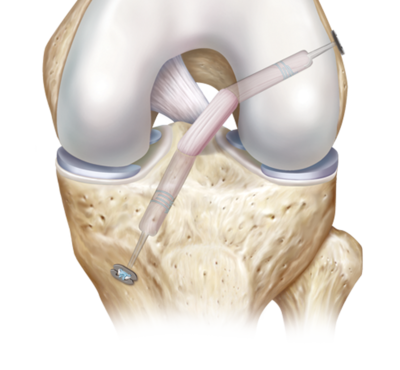

In cazurile severe sau cand ligamentul este rupt complet, poate fi necesara interventia chirurgicala pentru reconstructia sau repararea ligamentului afectat. Aceasta poate implica utilizarea grefelor sau a tesuturilor proprii pentru a restabili stabilitatea articulatiei.